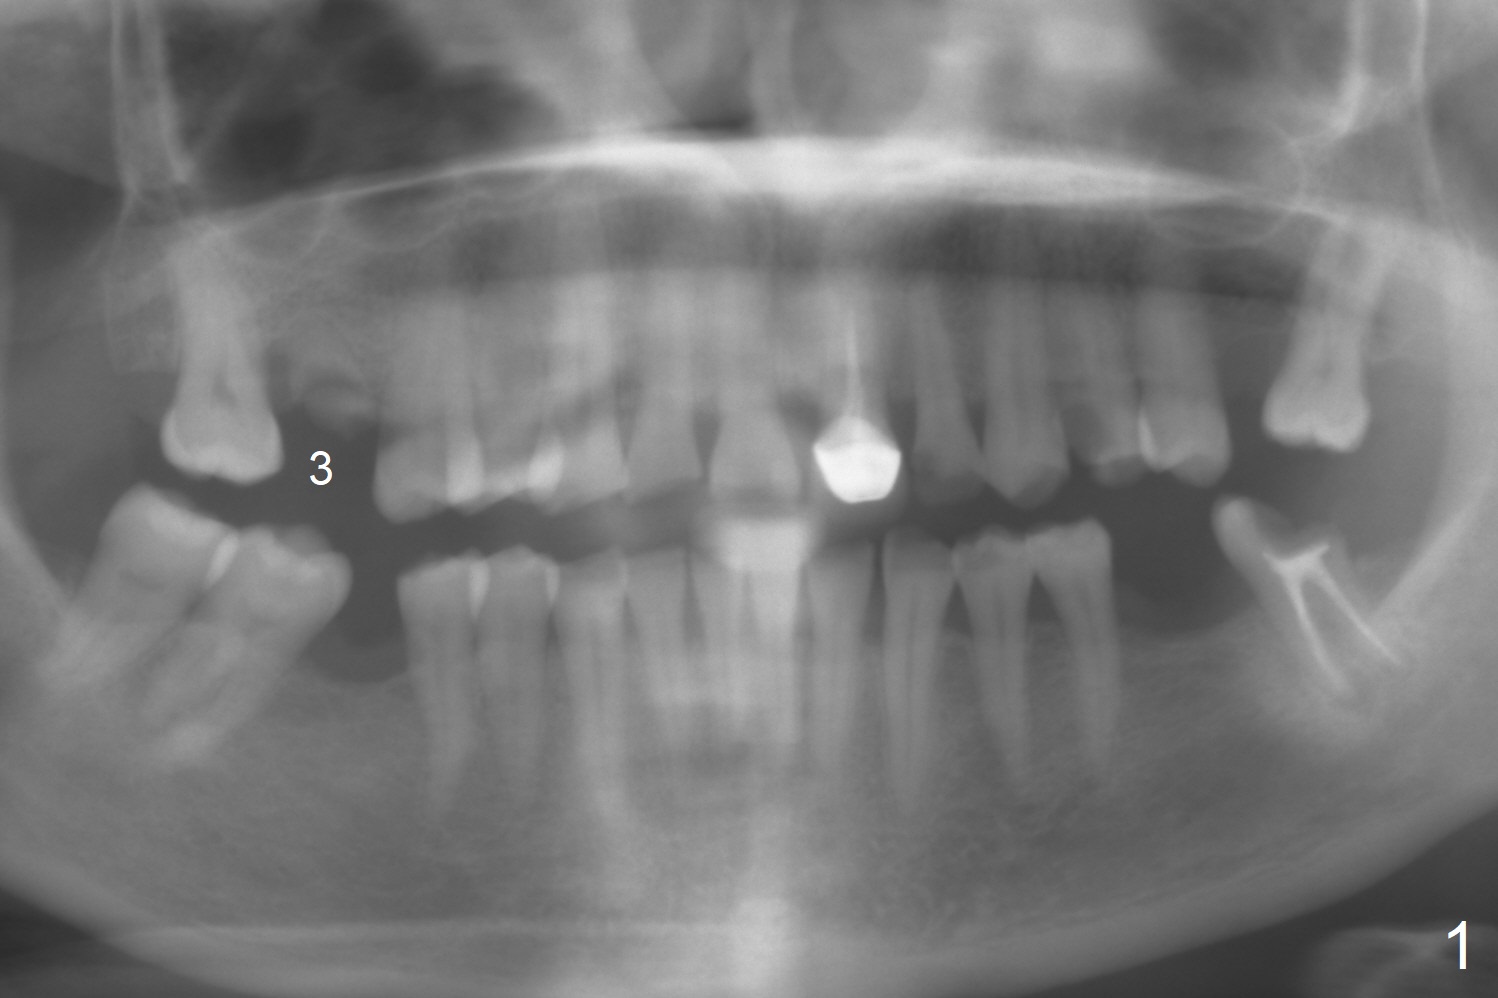

A 45-year-old woman has poor dentition due to dental phobia (Fig.1). The tooth #3 has residual roots (Fig.2 *). The initial depth will be 9 mm with starter drill, 2 mm drill (parallel pin, PA) and 3.2 mm Magic Drill (Fig.3). Use 4x11 mm dummy implant for sinus lift for the last 2 mm.